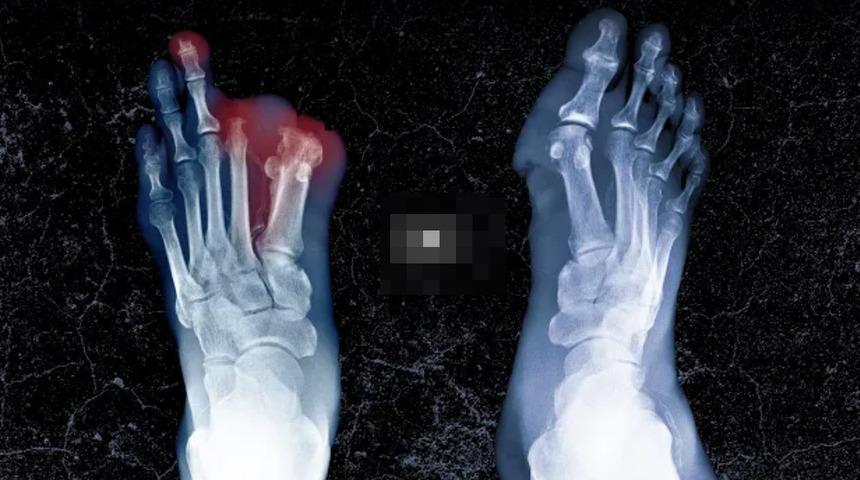

AMPÜTE EDİLMESİ GEREKTİ

Kan testleri sonuçları geldiğinde kanında Neisseria meningitidis adı verilen bir bakteri olduğu ortaya çıktı. Bağışıklık sisteminin tepki vermeye başladığını belirten Dr. Bernand, "Kanda bakteri bulunduğunda, vücudun tüm kan damarları genişler, kan basıncı düşer ve oksijenin organlara ulaşması engellenir" dedi.